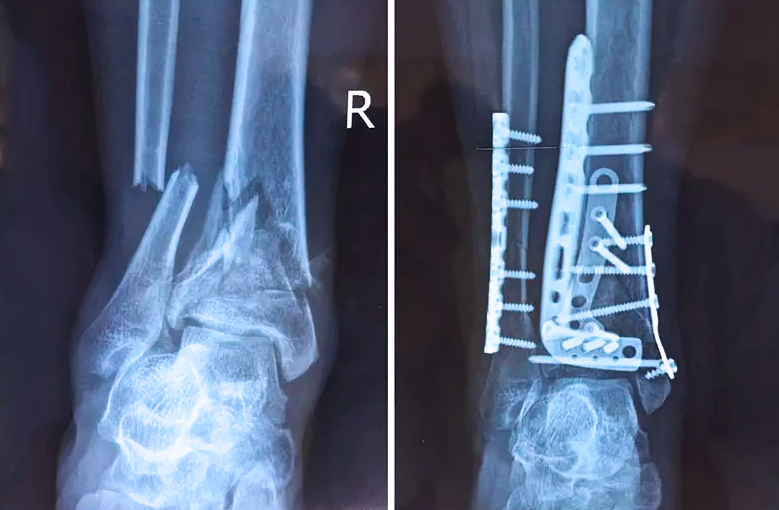

踝關節(jié)是人體中負重較大的關節(jié),也是活動度較大的地方,所以對于足踝部位的關節(jié)內(nèi)骨折,我們更需要做到“解剖復位”。對于這種關節(jié)內(nèi)的骨折,尤其是踝關節(jié)內(nèi)部的骨折,不僅需要進行X影像平片正側(cè)位的拍攝,由于在二維影像上無法判斷關節(jié)面的受損情況,往往還需要進行三維影像的檢查。

在術前,我們需要做三維掃描的CT檢查,我們必須要有CT的片子,還要有三維的重建。

在術中,我們怎么去判斷關節(jié)面平不平整呢?常規(guī)的正側(cè)位影像是不能判斷的。有些醫(yī)生為了準確的判斷,可能會選擇做開放性的手術,把關節(jié)暴露出來,在眼睛的直視下判斷關節(jié)面平不平整。但是關節(jié)全部打開,無疑增加了病人的創(chuàng)傷,而且增加了患者的恢復時間。所以如果在術中我們有三維影像的支持,對醫(yī)生做手術而言就會事半功倍,而且能夠大大的增加手術準確度,增加患者術后的預后。所以在術中有三維影像的支持是非常必要的!